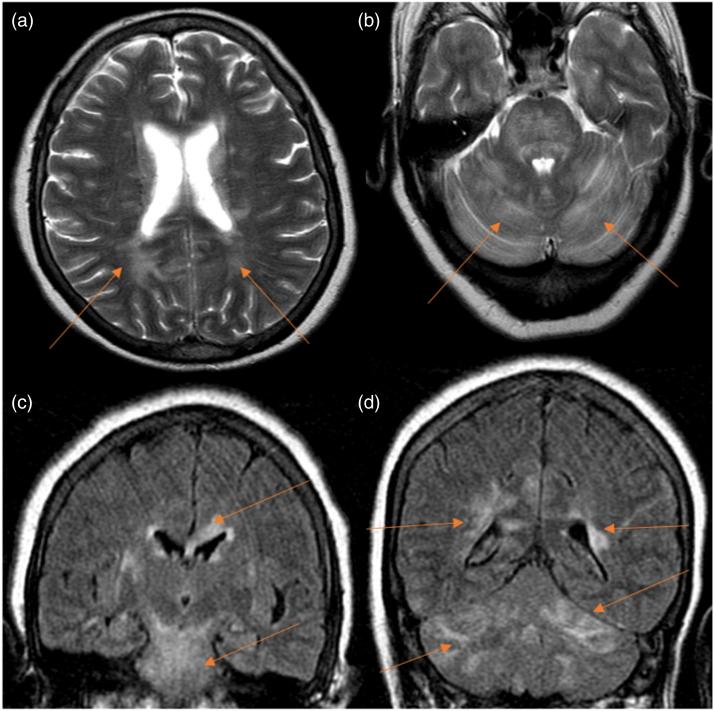

We found an elevated rate of neuroimaging findings in patients following LT with 32.6% of positive studies. In our cohort, the average time after LT to a neurological complication was 4.9 months post-transplant. Encephalopathy, critical illness polyneuropathy and stroke, in that order, were the most frequent neurological complications. Structural abnormalities in brain imaging were more often detected using MRI than CT for indications of encephalopathy and seizures.